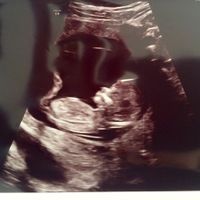

3262 giorni faEcco la translucenza fatta ieri ... è andata bene ora aspetto i risultati del bitest... ieri un emozione ancora più forte 😍